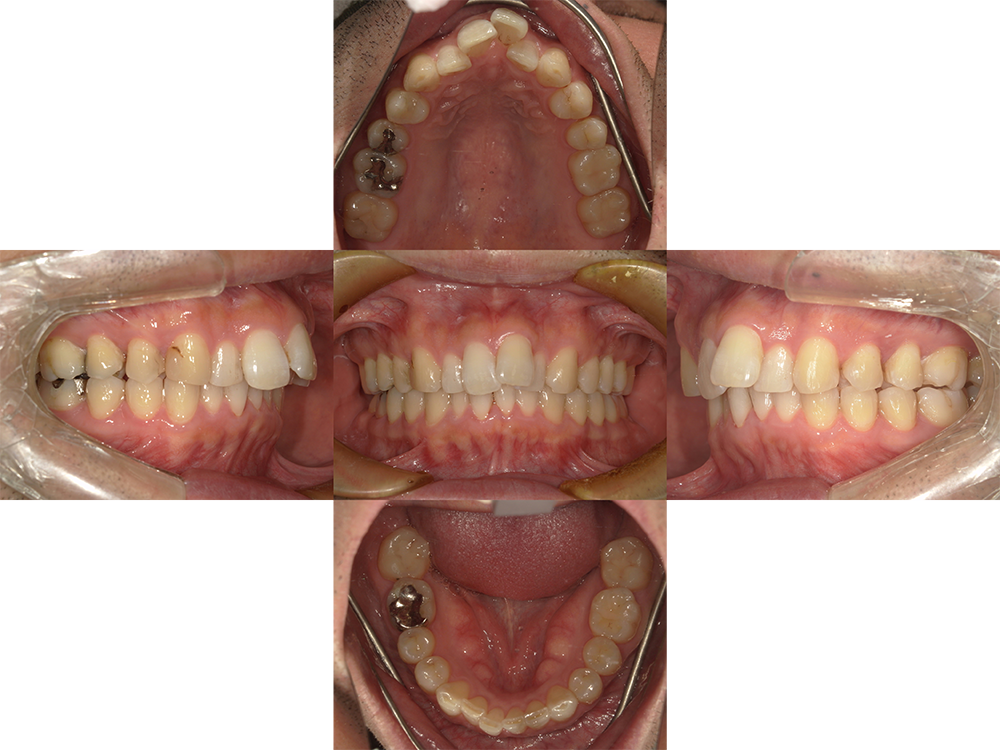

Before

After

主訴

叢生

装置

ワイヤー矯正

治療期間

2年2ヵ月(現在保定中)

性別

男性

年齢

40歳

抜歯箇所

上顎左右4番

費用

367,400円

非抜歯にてマウスピース矯正(インビザライン)を他医院から転勤にて転医。 インビザラインのアカウントを引継ぎ非抜歯にて治療を継続。

仕事の都合上、マウスピースを装着する時間が短いので治療が進まないとのことで、上顎左右4番の抜歯によるワイヤー矯正に変更することに。